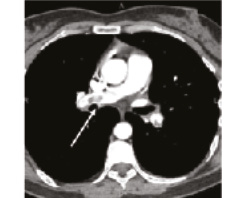

В 1993 г. на основании характерных признаков электрокардиограммы (ЭКГ) при профилактическом обследовании диагностирован феномен Вольфа–Паркинсона–Уайта. Клинических проявлений, снижающих качество жизни, пациентка не отмечала. К врачам далее не обращалась. В связи с появлением в 2015 г. одышки, перебоев в работе сердца, сердцебиения наблюдалась у участкового терапевта с диагнозом: ишемическая болезнь сердца, гипертоническая болезнь. Эхокардиография (ЭхоКГ), нагрузочные тесты не проводились. На фоне приема лозартана 25 мг/сут достигнуты целевые значения АД. В январе 2017 г. в связи с зарегистрированным на ЭКГ пароксизмом тахикардии с узкими комплексами QRS пациентка в порядке скорой помощи поступила с диагнозом «пароксизмальная суправентрикулярная тахикардия» в ЦРБ, где ритм был медикаментозно восстановлен. Далее в краевой больнице проведено внутрисердечное электрофизиологическое исследование и по его результатам – радиочастотная аблация дополнительных проводящих путей. Послеоперационный период протекал без осложнений. Однако в июне 2017 г. вновь появилась одышка при выполнении привычного объема физической нагрузки. По данным ЭКГ и рентгенограммы органов грудной клетки патологии не выявлено. Вскоре появилось кровохарканье (в течение 3 дней), и пациентка была направлена к фтизиатру, которым исключен туберкулез легких. 27.07.2017 на фоне значительного усиления одышки, выраженной тахикардии она потеряла сознание и в порядке скорой помощи доставлена в дежурный стационар, где травматологом и неврологом исключены сотрясение головного мозга и закрытая черепно-мозговая травма. Пациентка отпущена домой. В связи с сохраняющейся одышкой при подъеме на один лестничный пролет в августе 2017 г. по собственной инициативе она обратилась к кардиологу. При проведении ЭхоКГ выявлены увеличение правых камер сердца и признаки их объемной перегрузки. С предварительным диагнозом ТЭЛА пациентка направлена в дежурный стационар, где в экстренном порядке проведена спиральная компьютерная томография (СКТ) с контрастированием легочной артерии. Выявлены признаки легочной тромбоэмболии крупных и средних ветвей легочной артерии (ЛА) с обеих сторон (рис. 1–4). При целенаправленном сборе анамнеза выяснилось, что в течение 3 лет (с 2014 г.) пациентка принимает Линдинет 20 мг – монофазный пероральный контрацептив (этинилэстрадиол + гестоден), назначенный гинекологом с целью контрацепции. По данным ультразвукового исследования вен нижних конечностей выявлен тромбоз суральных вен справа. Линдинет отменен. На фоне лечения антикоагулянтами (гепарин, эноксапарин) состояние женщины несколько улучшилось. Она переведена на варфарин, который далее заменен на апиксабан в дозе 10 мг 2 раза в день.

СКТ с контрастированием ЛА | |

14.08.2018 | 26.09.2018 |

Рис. 3: а – тромбы в нижнедолевой ветви левой ЛА и нижнедолевой ветви правой ЛА; б – сохраняется тромбоз нижнедолевой ветви правой ЛА. | |

Рис. 4: а – тромбы в левой ЛА и ее ветвях; б – тромбоза левой ЛА (нисходящей ветви) не выявлено, сохраняется тромбоз нижнедолевой ветви левой ЛА. | |

По данным чресприщеводной ЭхоКГ тромбоза камер сердца не обнаружено, однако уровень D-димера – более 250 мкг/л. Исследования в отношении патологии гемостаза выявили значительный дефицит протеинов С и S. Проведена замена апиксабана на ривароксабан 15 мг 2 раза в сутки с последующим переводом на прием ривароксабана 20 мг 1 раз в сутки в связи с большей биодоступностью последнего. Также с целью усиления антитромботического эффекта к терапии добавлен клопидогрел в дозе 75 мг в сутки. При проведении СКТ органов грудной клетки с контрастированием легочной артерии 26.09.2018 выявлена положительная динамика (см. рис. 1, б, рис. 4). Состояние стабилизировалось, рецидивы одышки прекратились. От имплантации кава-фильтра пациентка отказалась.